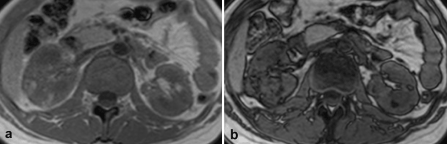

Moreover, the patient revealed multiple lesions in both kidneys, as found in abdominal ultrasound: Consecutive MR imaging confirmed the presence of multiple small lesions in both kidneys. These lesions showed high signal on T1-weighted in phase gradient-echo images and signal loss on opposed phase gradient-echo images (Figure 2), as found in fat containing benign tumors.

Figure 2. a: On T1-weighted gradient-echo in-phase imaging the lesions show high signal. b: On opposed-phase gradient-echo images the lesions reveal signal loss due to the presence of fat, as found in Angiomyolipomas.